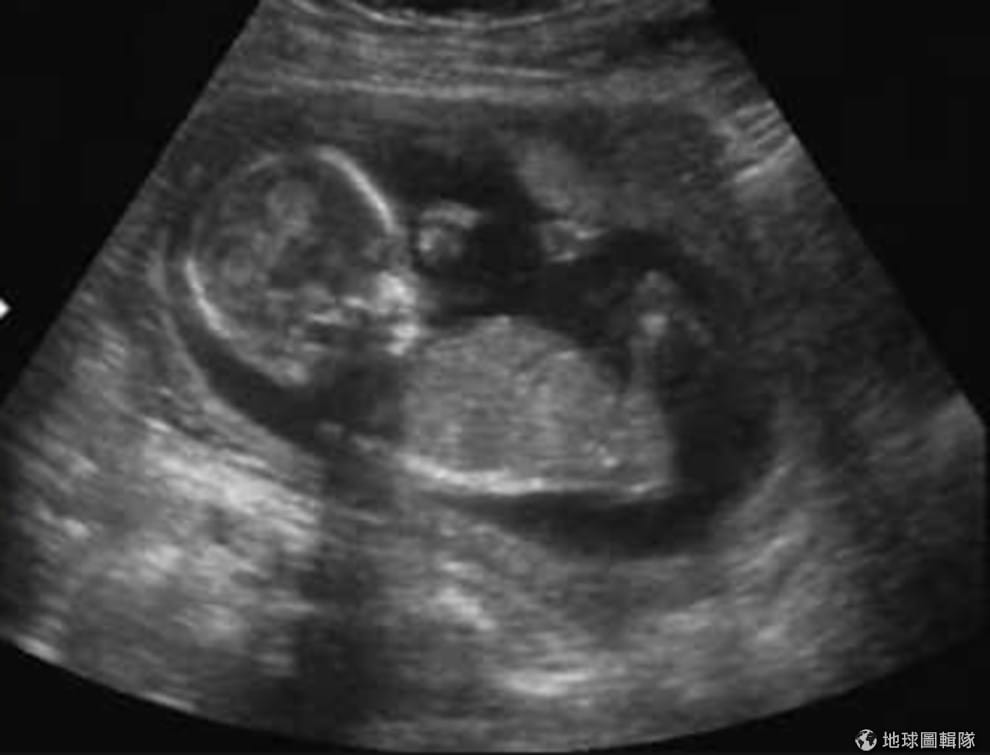

這是我第一眼看到我的女兒。

第一眼在超音波上見到她,她是怪物的小孩,卻是個天使

當第一眼看到她時,是在墮胎婦產科裡的超音波影像中,我存了好幾個月的錢才去成的,在努力存錢的這幾個月間,我也自我調適心情,準備面對即將席捲而來的兩種感覺。

最後,我終於看到超音波影像。這天距離我被強暴已經過了 17 週又三天了,過了好一段時間了,所以映入眼簾的不是當初那噁心的精蟲,我看到的是一個生命,是一個小孩,是我的嬰兒。

超音波師把儀器再放回我的肚子上移動了一下,嬰兒的影像再度出現,不知道為什麼,在眼淚中我竟然不由自主地微笑了。

「我無法理解,這麼可惡又噁心的怪物,怎麼能創造出這麼美麗的生命?」我說出口。